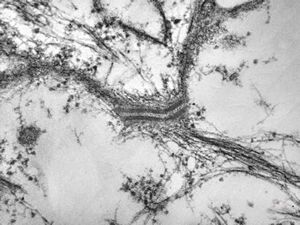

M,71y. | Alzheimer diseaseaccompanied with CADASIL

M,71y. | Alzheimer diseaseaccompanied with CADASIL

M,71y. | Alzheimer diseaseaccompanied with CADASIL